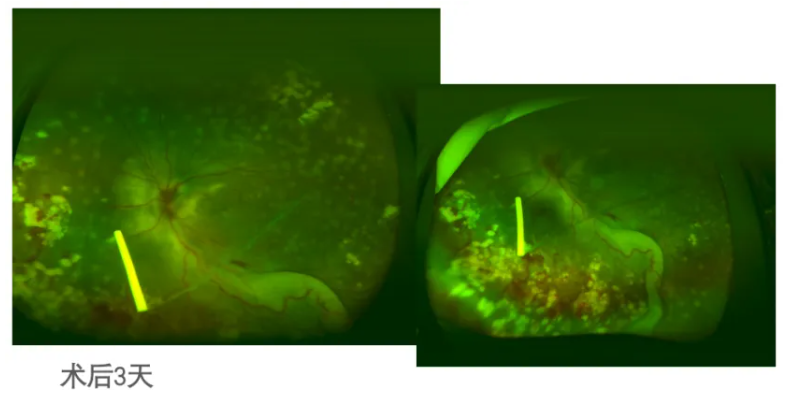

2022-10-25:左眼底PPV+激光+冷凝+糖皮质激素缓释药物

2022-10-28

2022-11-28

2023-03-27

2023-04:第一次左眼抗VEGF

2023-05-15:补充眼底激光(第二次)

2023-07-10:第二次抗VEGF

2023-08-17:视力FC/60cm, 虹膜NV;右眼眼压18mmHg,左眼眼压26mmHg

2023-08-18:第三次抗VEGF +第三次激光(眼内激光)

2025-09-29:末次随访